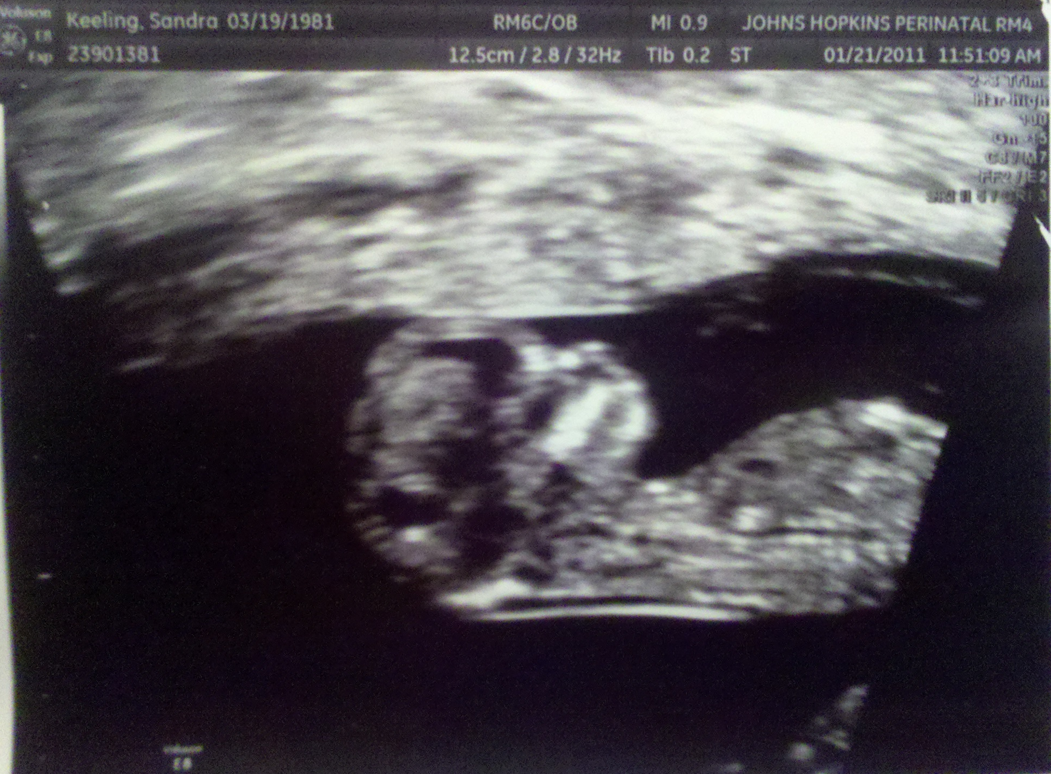

It's definitely a Keeling.

So there we are at our 2nd checkup since Sandi became pregnant.

We're excited to see the new ultrasound because he/she may look more like a baby and less like a seahorse.

We weren't disappointed.

The first view of Junior showed him standing straight up in his lovely living quarters.

Unfortunately, things were a weeee bit cramped as Mom's bladder was perhaps a bit more full than the nurse requested.

After a brief respite to give the little one a little more space, we tried again and saw the baby crouching carefully in the bottom right corner of the picture.

At first, me as the Father was a little curious of my spawn's desire to stay so still.

Then WHAMMO.

He/She sprang out of the corner, legs and arms extended, then just as quickly crouched back down.

The little one was screwing with us. Definitely a Keeling.

Here's the new bundle of joy.